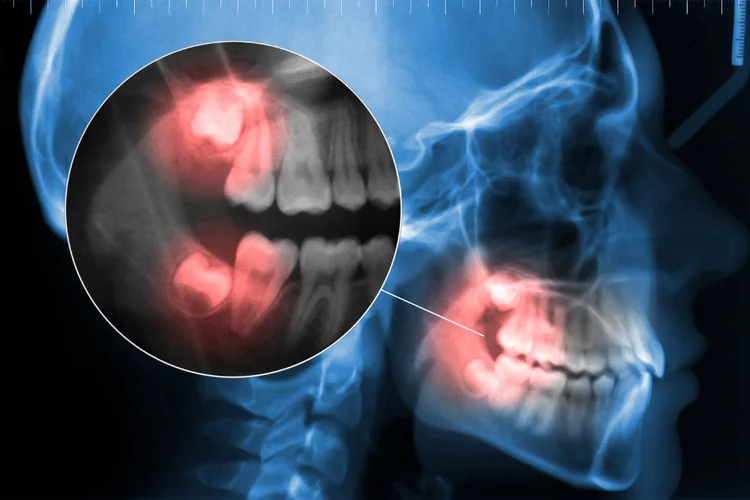

- Impaction – A wisdom tooth that is partially or fully trapped in the jawbone or gums, often leading to pain, swelling, and potential infection due to difficulty in eruption.

- Pericoronitis – Inflammation of the gum tissue around a partially erupted wisdom tooth, often leading to tenderness, swelling, and infection due to bacterial buildup.

- Pressure on Gum Tissues – As a wisdom tooth emerges, it may press against the surrounding gum tissues and cause inflammation. Occasionally, the erupting wisdom tooth on the upper jaw may press on the lower gums and cause ulcerations as well.

- Tooth Decay – Impacted wisdom teeth are harder to clean due to their position, allowing plaque buildup that increases the risk of cavities and further discomfort.